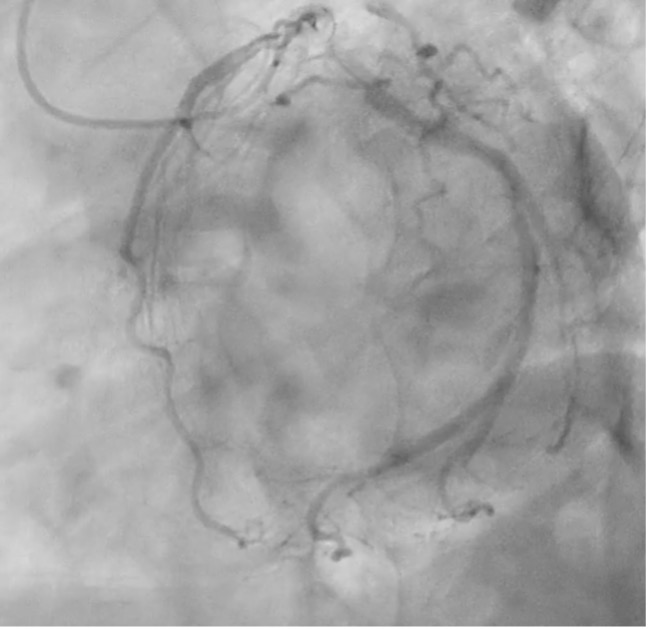

CAG shows mild diffuse stenosis at mid to distal LAD, severe diffuse stenosis at obtuse marginal, and mild diffuse stenosis at RCA (Pic 1, 2, 3).